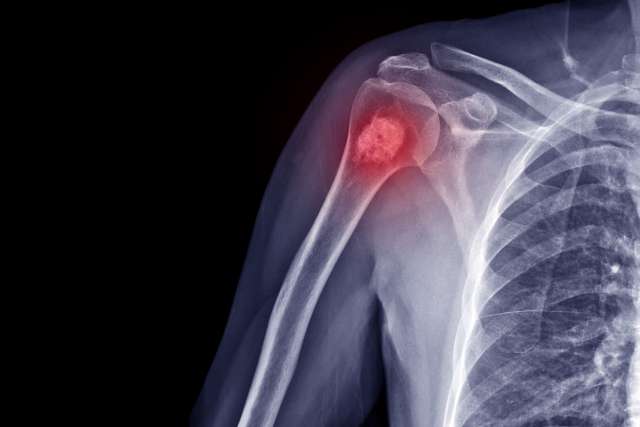

Orthopedic oncologists are doctors who treat the full range of cancerous (malignant) and noncancerous (benign) bone and soft tissue tumors, including:

Benign bone tumors

Malignant Bone Tumors

Cancerous growths that start in or spread to bones, including: